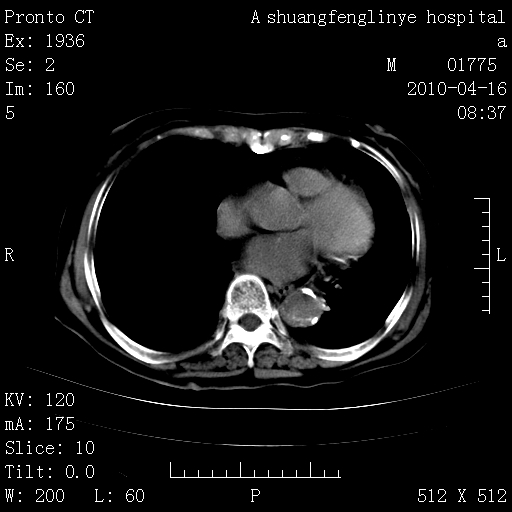

陈旧性结核,胃腔扩大,脾脏受压后移

典型 夹层动脉瘤。 内膜瓣钙化移位

1)左肺上叶结核(纤维、增殖病灶)。2)冠状动脉及主动脉钙化。肺动脉高压